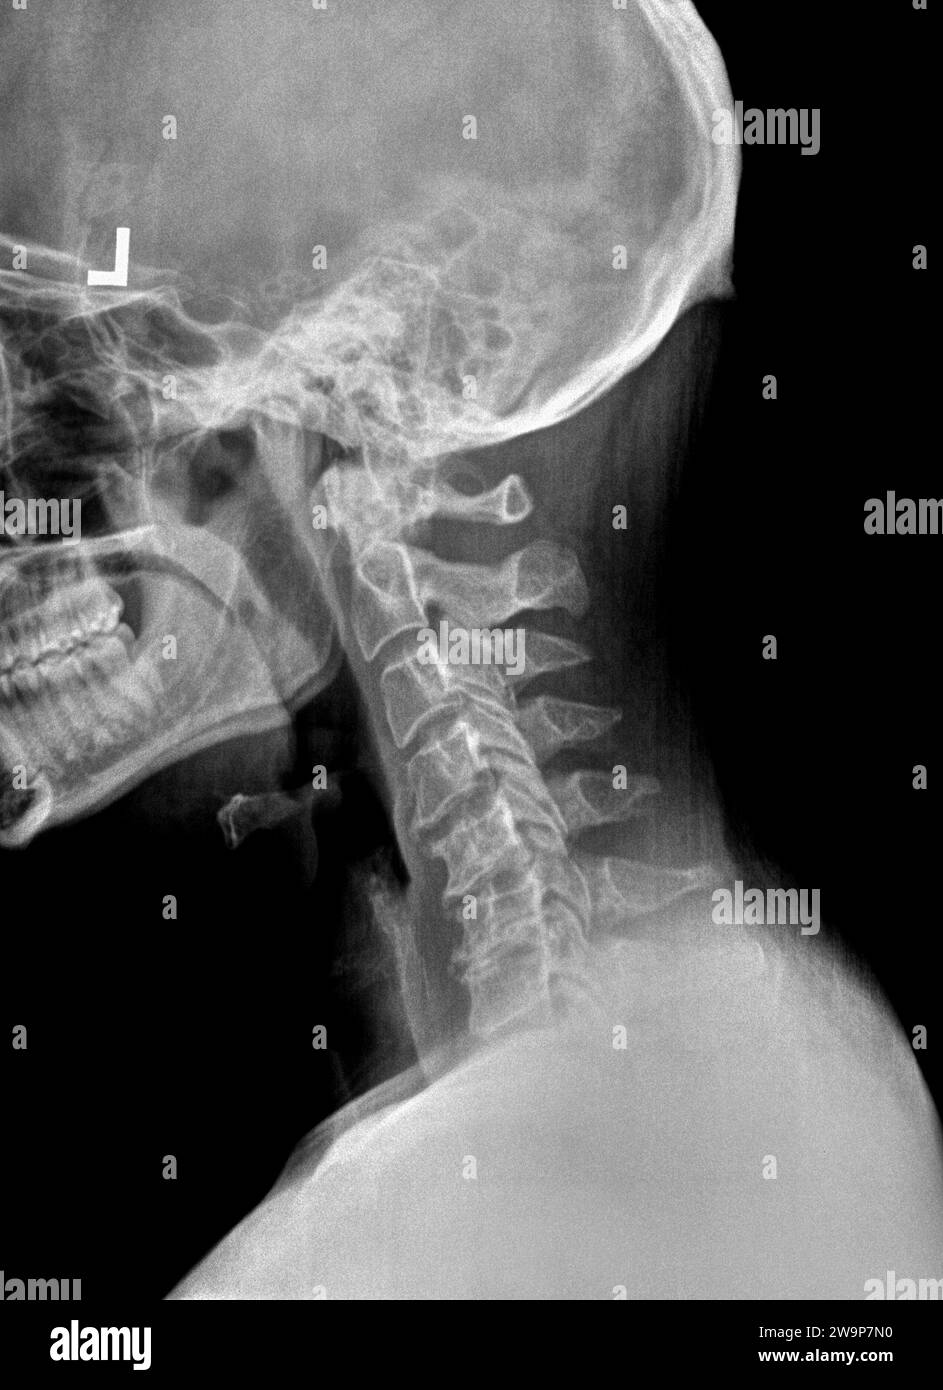

From www.alamy.com

Film x ray or radiograph of a cervical neck. Lateral side view showing Neck Cervical Kyphosis Before And After Reversed neck curve (when your neck curves in the opposite direction) cervical kyphosis is a condition that affects the curvature of the cervical spine, which is the portion of the. A crooked neck could mean that your cervical vertebrae have shifted out of. Other names for losing your neck's natural curve include: when you have cervical spine kyphosis,. Neck Cervical Kyphosis Before And After.